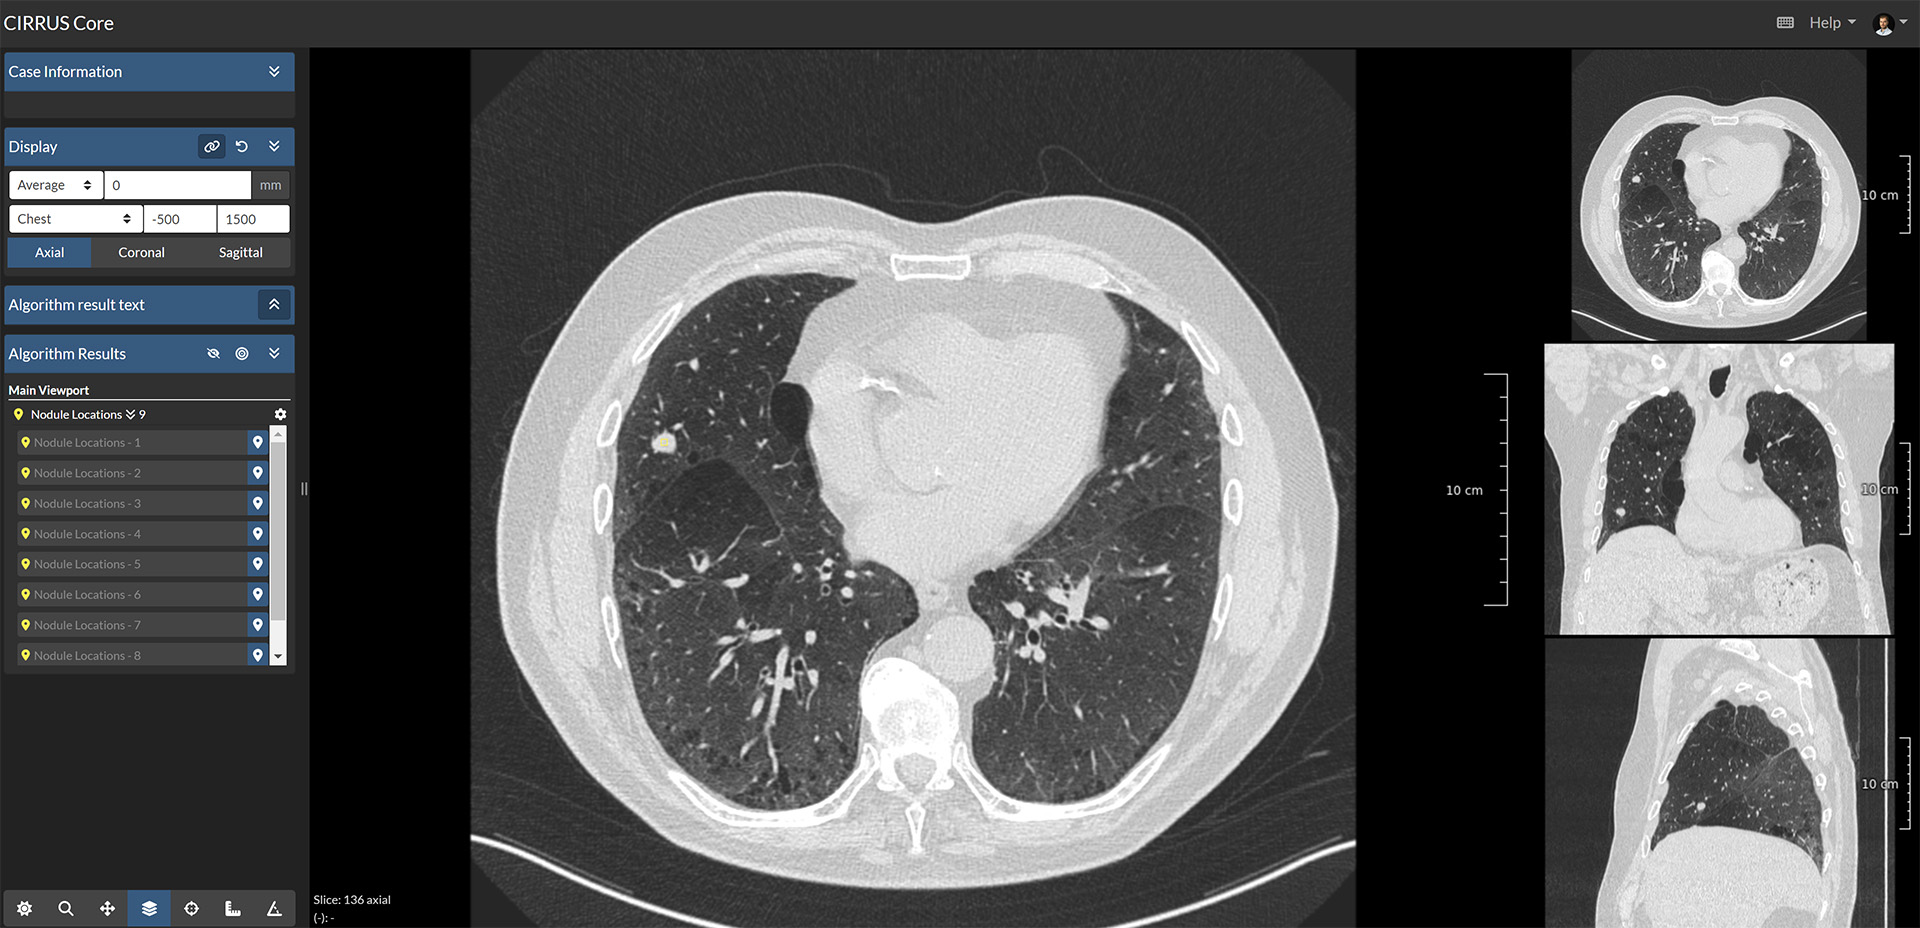

We developed a deep learning-based system and retrospectively assessed its performance for the detection of actionable benign nodules (requiring follow-up), small lung cancers, and metastases in CT scans acquired from a routine clinical setting in two Dutch hospitals (internal and external validation). Our nodule detection pipeline has three components: first, the system takes a CT scan and detects the lungs slice-by-slice to obtain a region of interest. Second, nodule candidates are generated by analyzing overlapping CT volumes of five slices each. Finally, nine different slices from a 3D patch around each nodule candidate are analyzed to determine whether a nodule is present. By employing this 2.5D detection approach, the system can quickly analyze the CT scan while preserving robustness to reliably distinguish nodules from lung vessels and other structures.

Overview of the proposed lung nodule detection system.

Algorithm availability

We made our AI system publicly available for research purposes on the web platform Grand Challenge. On this platform, the algorithm can be readily executed in the cloud and does not require the installation of any software. The algorithm takes a thorax or thorax-abdomen CT(A) scan as input, which can be provided as either a DICOM or MHA file. Then, it returns the location and corresponding likelihood score of any lung nodule. The nodules are highlighted as points in the scan, which can be inspected in a professional radiology workstation. Researchers can also download the complete algorithm outputs via the GC-API when many scans need to be analyzed. More detailed background and usage information can be found on the algorithm information page.

The algorithm is publicly available on the platform Grand Challenge.